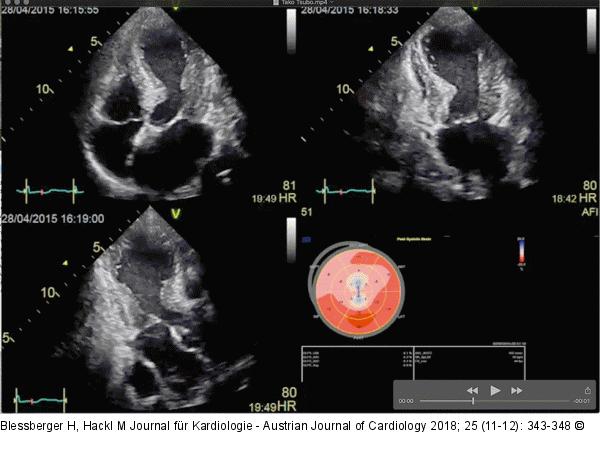

Abbildung 4: Linksventrikulärer longitudinaler Strain Apikaler Vier-, Zwei- und Dreikammerblick und zugehörige „Bull’s Eye“-Darstellung des linksventrikulären longitudinalen Strains. Das Muster mit eingeschränkter Kontraktilität am Apex und den mittleren Segmenten sowie erhaltener Kontraktilität an der Basis ist typisch für die Tako-Tsubo-Kardiomyopathie. |

Abbildung 4: Linksventrikulärer longitudinaler Strain